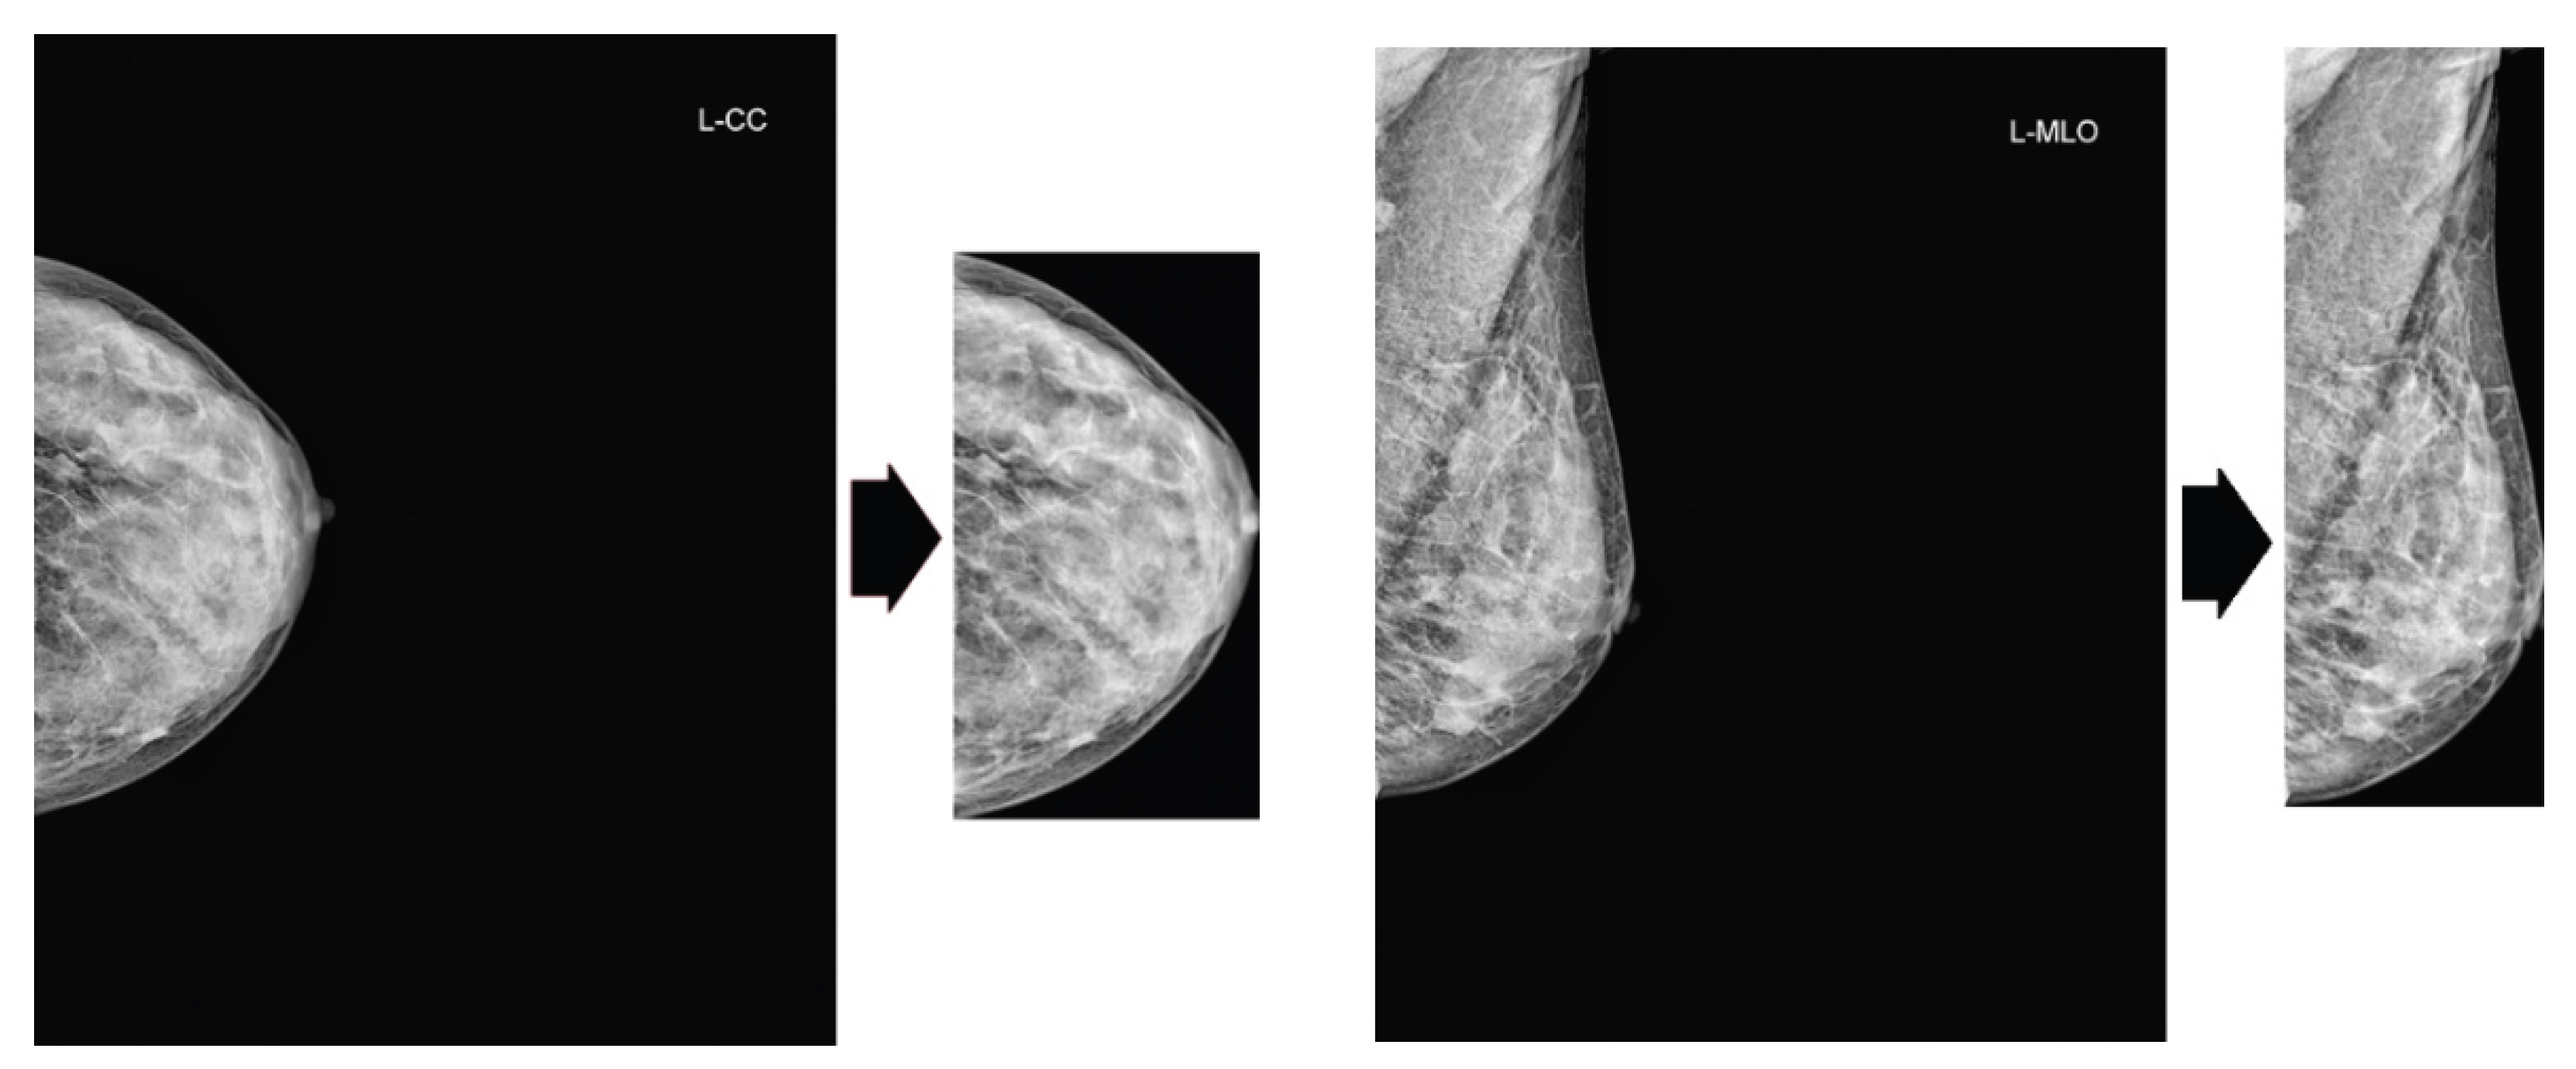

2.2. Preprocessing

Our preprocessing pipeline comprises two sequential steps. First, we apply Contrast Limited Adaptive Histogram Equalization (CLAHE) to mammogram images to enhance local contrast. Subsequently, we crop the excess black background from the images, as portrayed in Figure 2.

Figure 2. Cropping of excess black background. Original images are from the VinDr dataset.